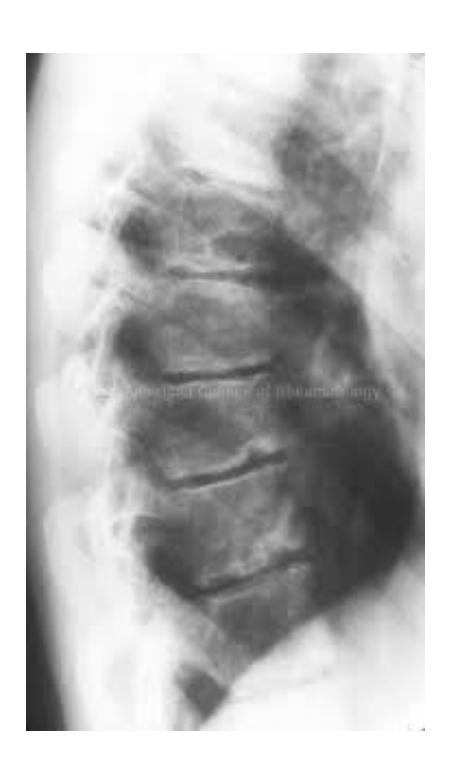

Describe: Schmorlโs Node etc.

Diagnosis: Scheuermannโs Disease